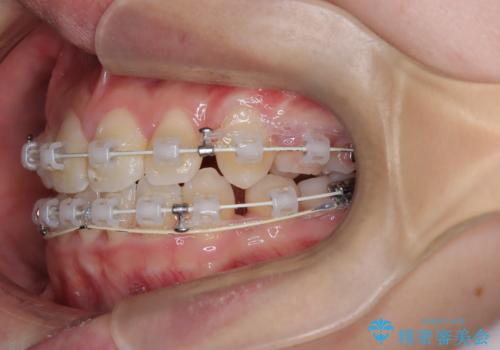

【埋伏歯】犬歯の牽引を行った矯正歯科治療

- 八重歯を主訴に来院されました。

左側犬歯が埋伏していましたが、第一小臼歯(4番目の歯)を抜歯したことでできたスペースに牽引し、右側の飛び出した八重歯を含め、歯全体を整列することができ患者様も満足していただきました。

犬歯牽引を行うかはCTを撮影し判断を行なっています。